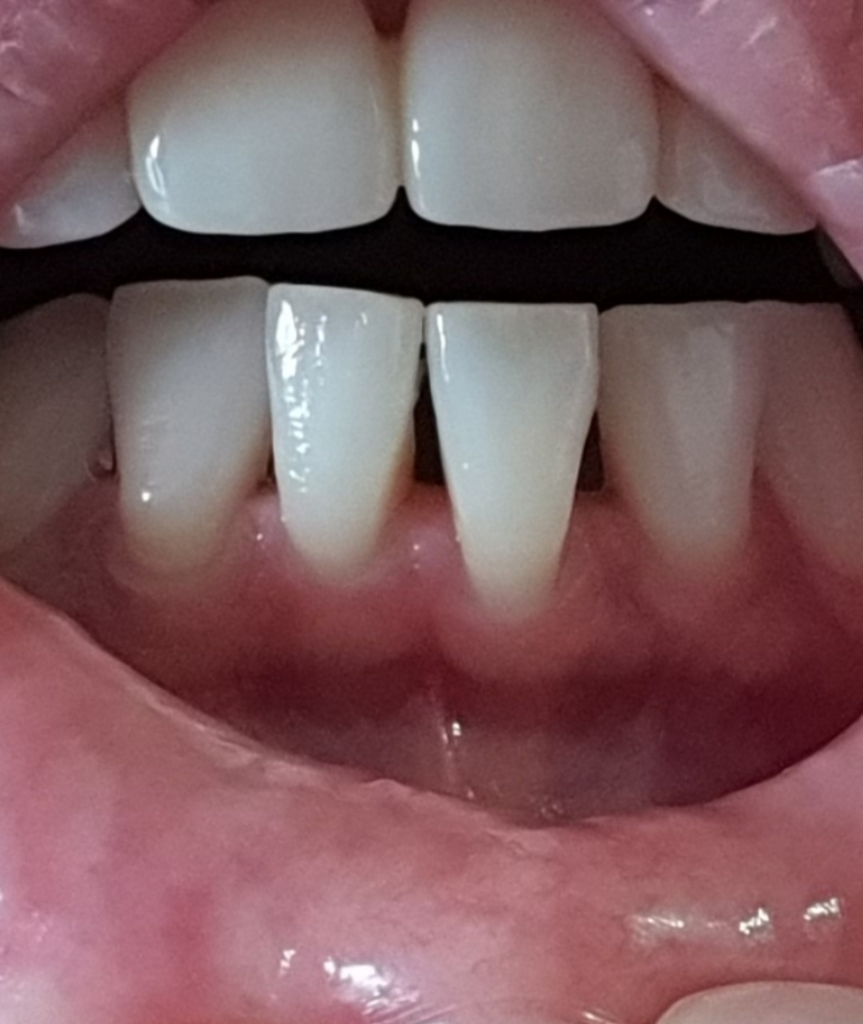

10년이나 지나서 그런지 이미 치열은 틀어졌습니다.

치아 뿌리도 너무 짧구요

블랙트라이앵글도 심합니다

잇몸도 내려갔습니다.ㅠ